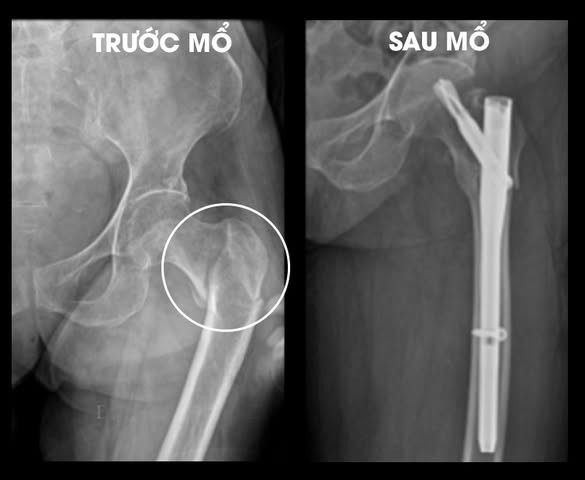

| Đóng đinh nội tủy chữa gãy liên mấu chuyển xương đùi tránh di chứng - Ảnh BVCC |

| Hình ảnh gãy xương trước và sau điều trị - Ảnh BVCC |